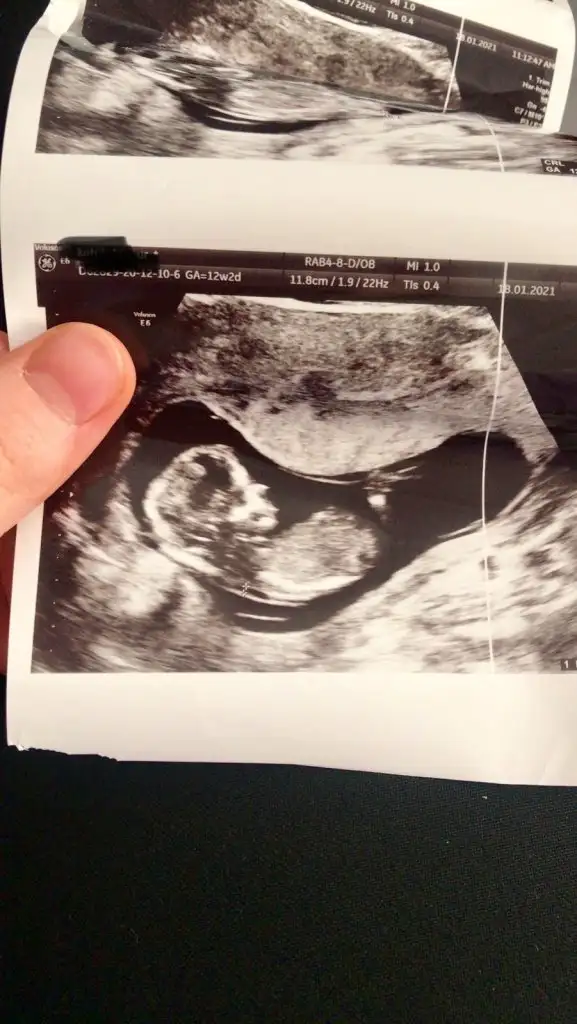

Buradaki hanımların nub teorisine göre kız gibiEki Görüntüle 2764421 Eki Görüntüle 2764422 Eki Görüntüle 2764423 Tahminde bulunur musunuz arkadaşlar